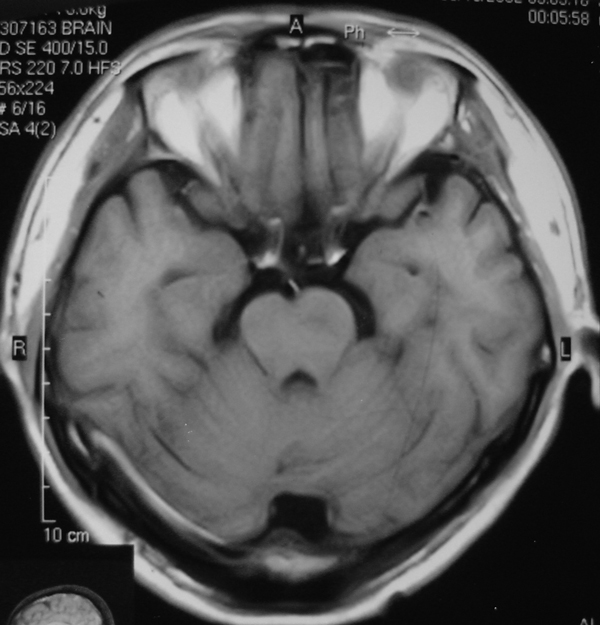

男 49岁 脑干腔隙梗塞5年。

这患者脑干(脑桥)腔隙脑梗塞是肯定的 有20002年资料 明天上传全部资料(当时工作忙 来不及)

1 单纯此图像定脑干梗塞依据不足. 2 可薄扫或核磁检查.

诊断依据不足,建议磁共振检查,

做磁共振吧!

脑干中脑区的梗塞还是能诊断的,建议薄扫一下。或者mri检查

脑干梗塞在ct上是斑点状低密度,一般只能在桥脑或中脑才能显示,延髓是很难发现(伪影多)。mr上脑干梗塞应该是长t1长t2的斑点状表现。弥散能够发现早期梗塞灶,表现高信号。

而小脑脚有三部分:①小脑下脚(绳状体)由脊髓小脑束组成, ②小脑中脚(脑桥臂)由脑桥小脑束组成, ③小脚上脚(结合臂)由出小脑纤维组成。小脑脚是正常神经纤维束构成,所以ct上密度是正常的(因为ct尚不能分辨脑干的细小神经纤维束);mr上是与正常白质一样的信号,而不是长t1长t2信号。

mri的优势